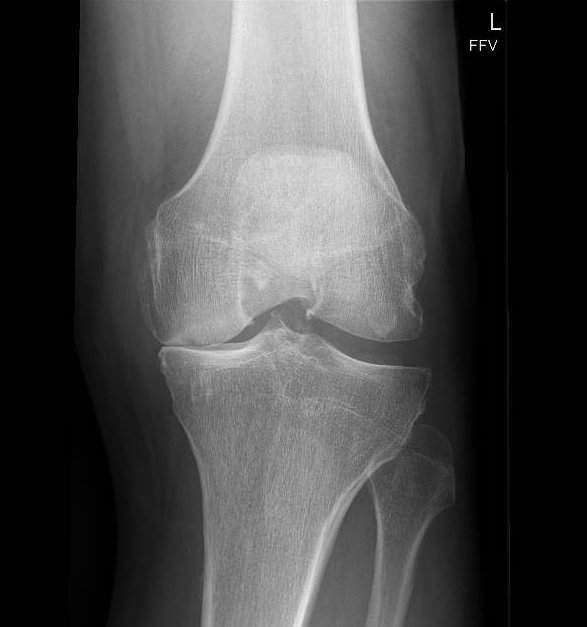

Een röntgenfoto werkt met straling die makkelijk door zachte weefsels heen gaat, maar wordt tegengehouden door dichte materialen. Botten bevatten veel kalk en zijn daardoor heel compact; zij houden de straling tegen en kleuren wit op de foto.

Kraakbeen bestaat echter voor het grootste deel uit water en eiwitten. Omdat kraakbeen geen kalk bevat, gaat de röntgenstraling er dwars doorheen, net als bij huid en spieren. Op de röntgenfoto lijkt het kraakbeen daarom "lucht" of een zwarte lege ruimte.

Juist die zwarte ruimte is voor de arts de belangrijkste informatiebron:

- Veel zwart tussen de botten? Dan zit er nog een gezonde, dikke laag kraakbeen die de straling doorlaat.

- Geen zwart (bot-op-bot)? Dan is het kraakbeen weggesleten en is er sprake van artrose.

Bij deze foto ziet u dat die ruimte aan één zijde bijna verdwenen is. Het bot komt daar direct op het andere bot, wat de pijn en stijfheid verklaart. Het contrast tussen de "open" gezonde kant van de knie en de "vernauwde" artrose kant knie maakt de diagnose voor iedereen direct begrijpelijk.